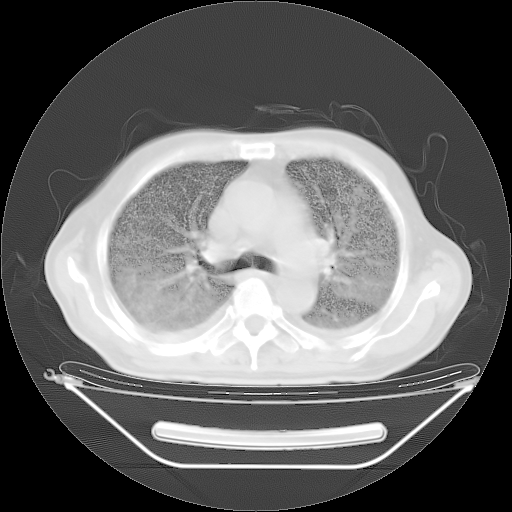

今天复查肺部CT,发现双肺广泛磨玻璃样改变。所以我把3月19日和5月9日相隔50天的肺部CT上传。请大家会诊。

5月9日肺部CT(在4月27日齐鲁医院肺部CT描述部分肺组织磨玻璃样改变,12天后肺组织广泛磨玻璃样改变)

2009年5月9日肺部CT

大致读了系列胸部CT:纵隔窗无明显异常,肺窗:从4、27至今:主要是双肺中下野外带可见毛玻璃样改变,目前处于急性肺泡炎阶段,至于原因考虑1、结替组织或胶原血管性疾病所致?2、恶性疾病如恶组在肺部所致的表现或细支气管肺泡癌?3、药物或其它原因如肺蛋白沉着症所致肺泡炎目前不太可能?总之,明天就去请我院的呼吸科、感染科、血液科和临免专家会诊哈。